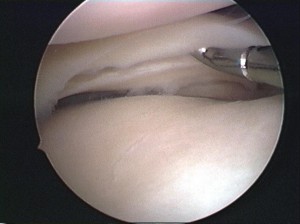

損傷した半月板(左図)に糸をかけて縫合した状態(右図)